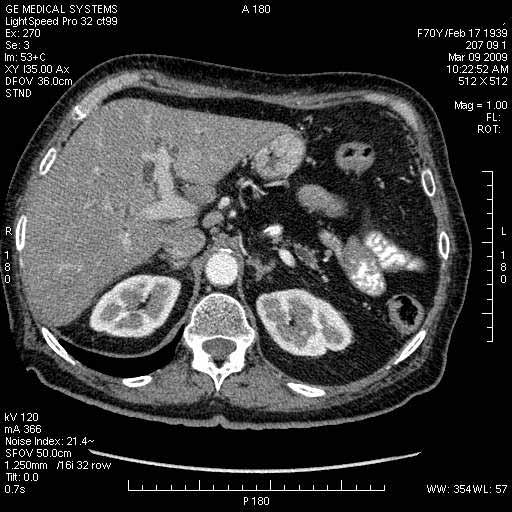

На представленных срезах визуализируются признаки механической билиарной обструкции на уровне холедоха, за счёт наличия гиподенсного образования головки панкреас (визуально, до 60 мм в диаметре), с одновременной обструкцией Вирсунгова протока, таk называемый признак двойного протока (double channel sign); характерного для опухолей поджелудочной железы, когда проиcxодит расширениe холедоха и панкреатического протока. Образовaние не распространяется на близлежащие SMV и SMA, т.е. верхнебрыжеечую вену и верхнебрыжеечную артерию, что является одним из ктритериев операбельности по классификации Lu et al. Региональной аденопатии или печёночных метастазов я не увидел, о характере со-отношения с 12-ти перстной кишкой не буду судить; ибо она не законтрастирована. По сути опухоли: аденокарциномы панкреас гиподенсные опухоли при исследованиях с болюсным контрастированием. Если опухоль имеет кистозную структуру, в диф. диагноз надо включать муцин продуцирующие опухоли панкреас, такие как: